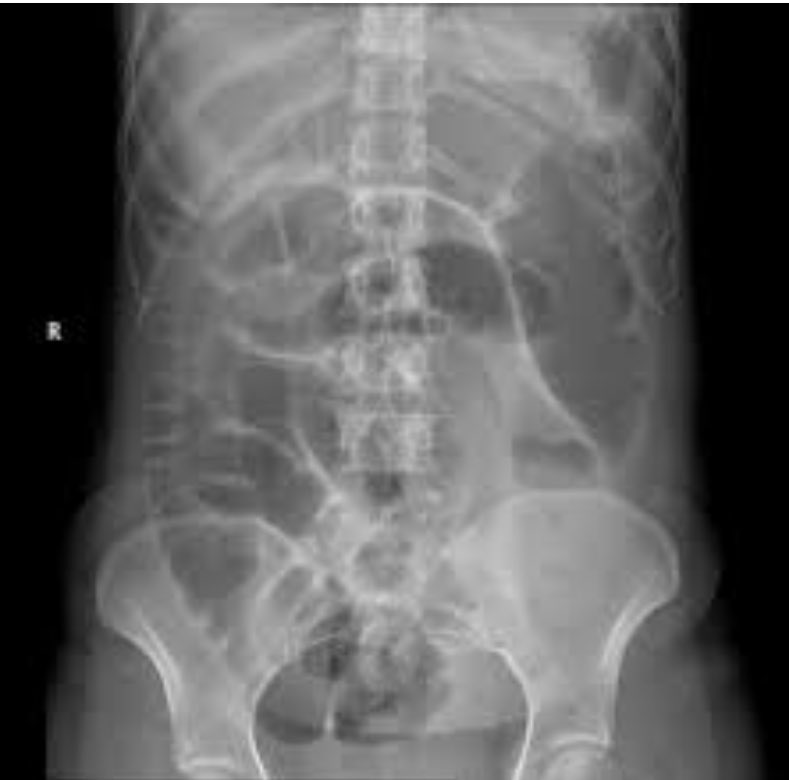

Very proud to publish this research with @ZielinskiTrauma at the @MayoClinic. "Small Bowel Obstruction Managed Without hospital admission: A Safe Way to Reduce Both Cost and Time in the Hospital?". Check it out here